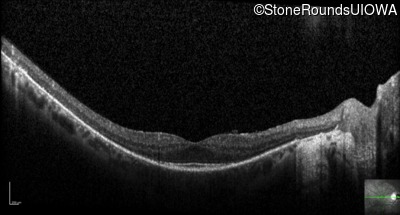

Optical Coherence Tomography - Right - 20/20

Exemplar / OCT Stack

OCT Stack